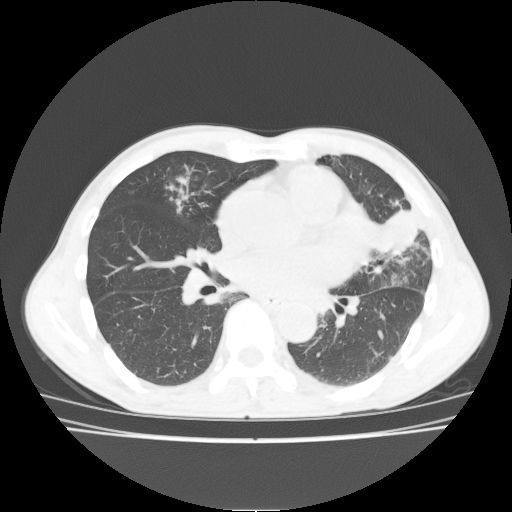

标题: CT25795:感冒后反复咳嗽两月余,痰中带血半月余。X诊断“肺 [打印本页]

标题: CT25795:感冒后反复咳嗽两月余,痰中带血半月余。X诊断“肺

1.双肺肺梗塞(理由:病灶呈三角形,与胸膜相连且局部胸膜肥厚,左心室增大)伴肺感染。

2.一元论双肺感染。

肺梗塞虽然有创意,但不现实。我考虑感染性病灶。

考虑两肺感染性病变,左肺上叶舌段肿瘤性病变待排;建议抗炎治疗后复查。